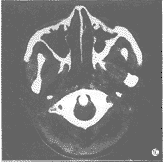

咽旁及颈动脉鞘区复发:肿瘤主要在咽旁、颈动脉鞘区生长,致咽旁、咽后间隙及颈动脉鞘区结构较前次CT所见更模糊或密度增高,或肿块出现。而咽壁增厚,咽腔缩小不明显。本组28例,占38.4%(图1)。

图1 A.鼻咽各壁增厚占位,双侧咽旁软组织内及颈血管鞘前区受侵。

B.经放射治疗后示鼻咽各壁呈正常改变。C.复查CT片示左侧颈血管鞘区及

左侧咽旁软组织内肿瘤复发占位,左侧咽旁间隙狭窄